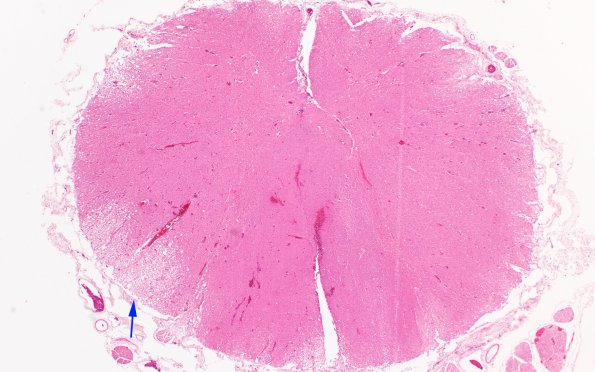

Washington University Experience | PERIPHERAL NEUROPATHY | 10 INFECTION | 2 Cytomegalovirus (in AIDS) | 2E1 CMV (Case 2) Spinal cord 2X copy

2E1,2 There is also extensive CMV involvement of the subpial portion of the brainstem and spinal cord (shown here). The area (arrow, 2E1) is shown at higher magnification in image #2E2. (H&E)